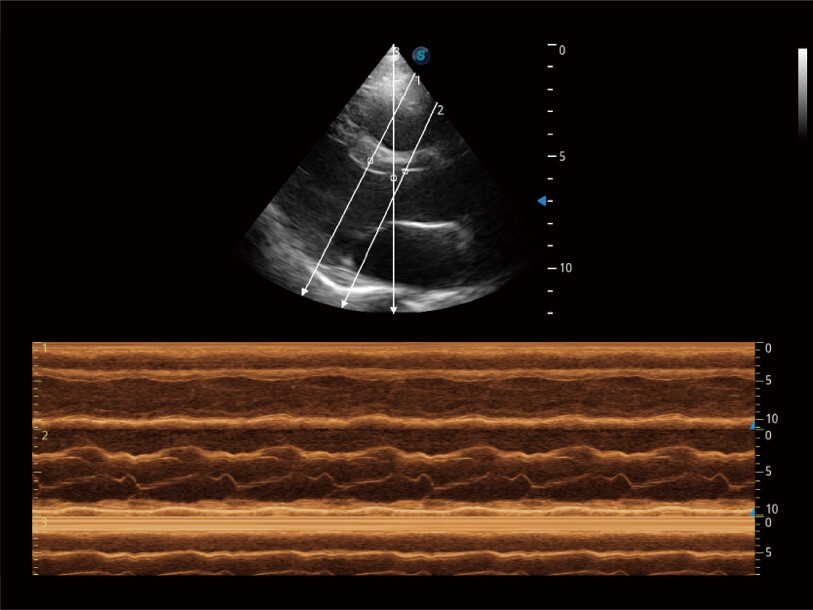

Erfasst Daten mit bis zu 3 Messlinien auf einmal, um die Wandbewegung detailliert beurteilen zu können. Verbessert die Reproduzierbarkeit und Genauigkeit der linksventrikulären Messwerte erheblich.

Ausgestattet mit dem gesamten Sortiment an Phased-Array-Schallköpfen von SonoScape (S1-5, 7P-A, 8P1), hochentwickelter Verarbeitungstechnologie und modernsten kardiologischen Tools bietet die ProPet-Serie Tierärzten eine umfassende ABklärung der Herz- und Myokardfunktionen.